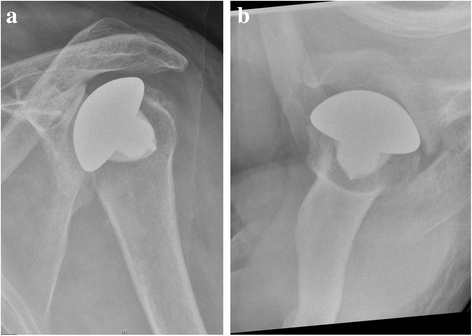

Background: Arthroplasty is a proven treatment option for glenohumeral osteoarthritis. Common indications include primary or posttraumatic osteoarthritis, avascular necrosis of the humeral head, rotator cuff tear arthropathy and rheumatoid osteoarthritis. Arthroplasty is rarely performed among patients with glenohumeral dysmelia. An overuse of the upper limb in patients with thalidomide-induced phocomelia and people with similar congenital deformities like dysmelia results in premature wear of the shoulder joint. This study aims to evaluate our experience with cases of glenohumeral osteoarthritis caused by dysmelia and treated with arthroplasty. To date, few reports on the outcome of shoulder arthroplasty exist on this particular patient group.

Case presentation: We included four dysmelic patients (five shoulders) with substantial glenoid dysplasia in a prospective database after approval by the local ethics committee. Once conservative treatment options had been exhausted, the patients were treated with shoulder arthroplasty and assessed clinically and radiographically before and after surgery. The mean patient age at the time of surgery was 50.4 years. The minimum follow-up time was 24 months (24-91 months). All patients experienced a considerable improvement of range of motion (ROM) and a relief of pain. No intra- or postoperative complications appeared.

Conclusion: Patients with dysmelia have acceptable short and mid-term results with resurfacing hemiarthroplasty. It is an effective although somewhat complicated method to relieve pain and improve movement. Long-term performance of arthroplasty in patients with dysmelia remains to be seen, particularly with regard to the remaining problem of the altered and often deficient glenoid.